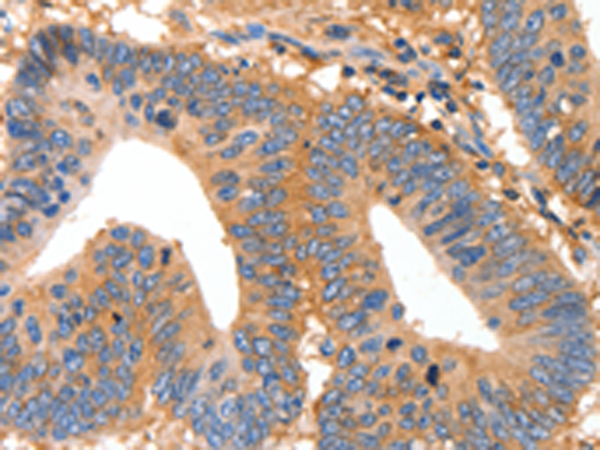

分类: 科研抗体货号: P11265别名: MUC-6应用: IHC反应种属: Human